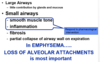

Emphysema